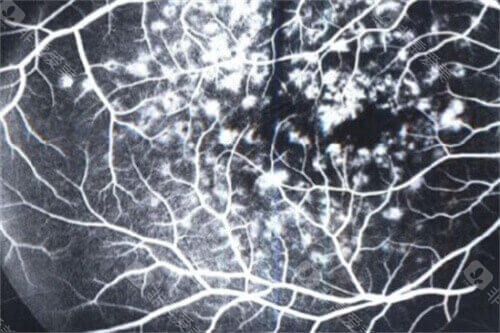

术前,患者需接受超全眼科检查,包括视力测试、眼底检查和OCT扫描,以评估病情并制定手术方案。

首可靠行玻璃体切除,清除眼内玻璃体以提供清晰视野;随后使用特定染色剂(如亮蓝)使黄斑前膜显色,便于比较准操作。

在显微镜下,医生用精细工具(如视网膜钩或镊子)小心抓住并剥离前膜,尽量减少对视网膜的损伤。